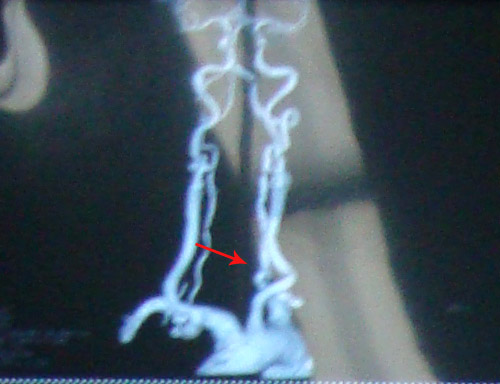

头颈部CTA示:头颈部动脉粥样硬化改变;右侧颈内动脉起始部重度狭窄约95%,双侧颈内动脉虹吸部中度狭窄;右侧椎动脉起始部轻度狭窄。

颈动脉超声示:双侧颈动脉内中膜增厚并多发斑块形成;右颈内动脉起始部弥漫性狭窄(重度)。